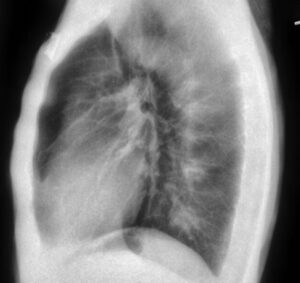

KA Imaging’s patented SpectralDR technology allows for clear differentiation between bone and soft tissue without motion artifacts, all within a single X-ray exposure. For example, in a chest X-ray, technicians can access an image of the lungs with the ribs subtracted. This greatly assists in diagnosis, removing obstructions (like bones) that can hide important medical information. Below is an example of three images produced with a single exposure using Reveal 35C. The example highlights a lateral view, not available with older dual-energy technologies:

soft tissue dual energy image spectraldr vs. bone suppression technology